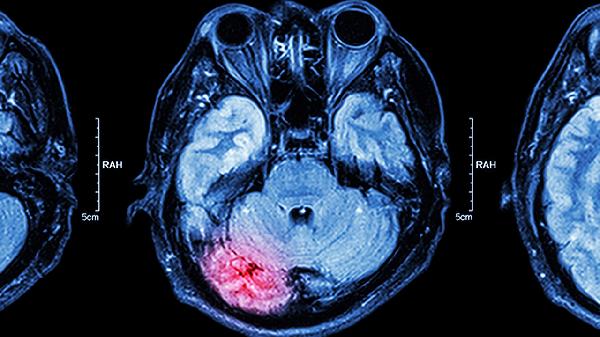

脑内微小动脉玻璃样变会导致慢性缺血,表现为反应迟钝、情绪波动。确诊需通过头颅MRI检查,可遵医嘱使用尼莫地平片、丁苯酞软胶囊等改善脑循环药物。